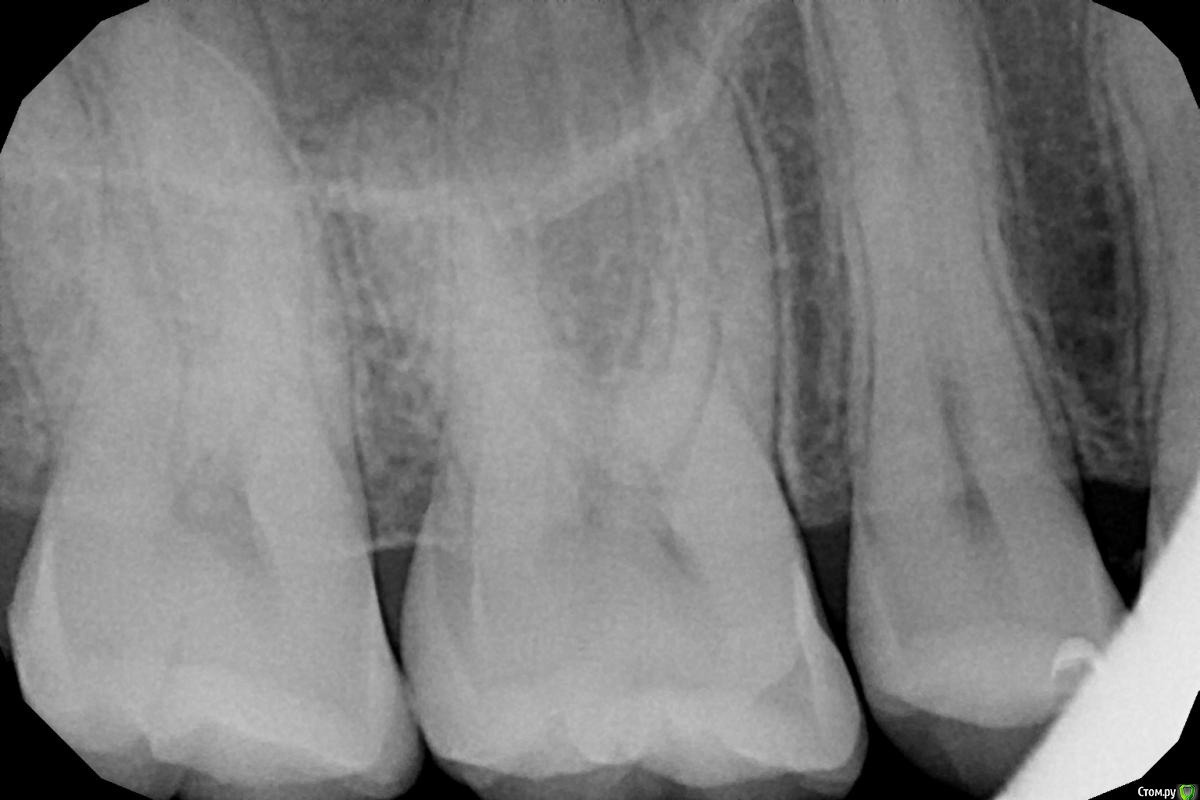

aleksandrovna_o Опубликовано 1 октября, 2020 Поделиться Опубликовано 1 октября, 2020 Здравствуйте, уважаемые врачи. Решила перестраховаться.Доктор, посмотрев на прицельные снимки, сказала, что есть кариес в двух местах. Один - его прямо срочно-срочно надо лечить, а другой - можно подождать максимум пол года. НО, у меня вообще там ничего не болит, нет реакции на горячее холодное, когда ем. Это как? такое разве бывает? посмотрите, пожалуйста, на снимки и скажите, действительно ли срочно нужно лечить.Первые два снимка - зубы 46-47. Там, если не ошибаюсь, кариес между зубами.Третий снимок — зубы 15,16,17.Буду очень признательна. Ссылка на комментарий

red_butler Опубликовано 1 октября, 2020 Поделиться Опубликовано 1 октября, 2020 Первые два снимка - зубы 46-47. Там, если не ошибаюсь, кариес между зубами. есть и кариес и камни такое разве бывает? еще как бывает 1 Ссылка на комментарий